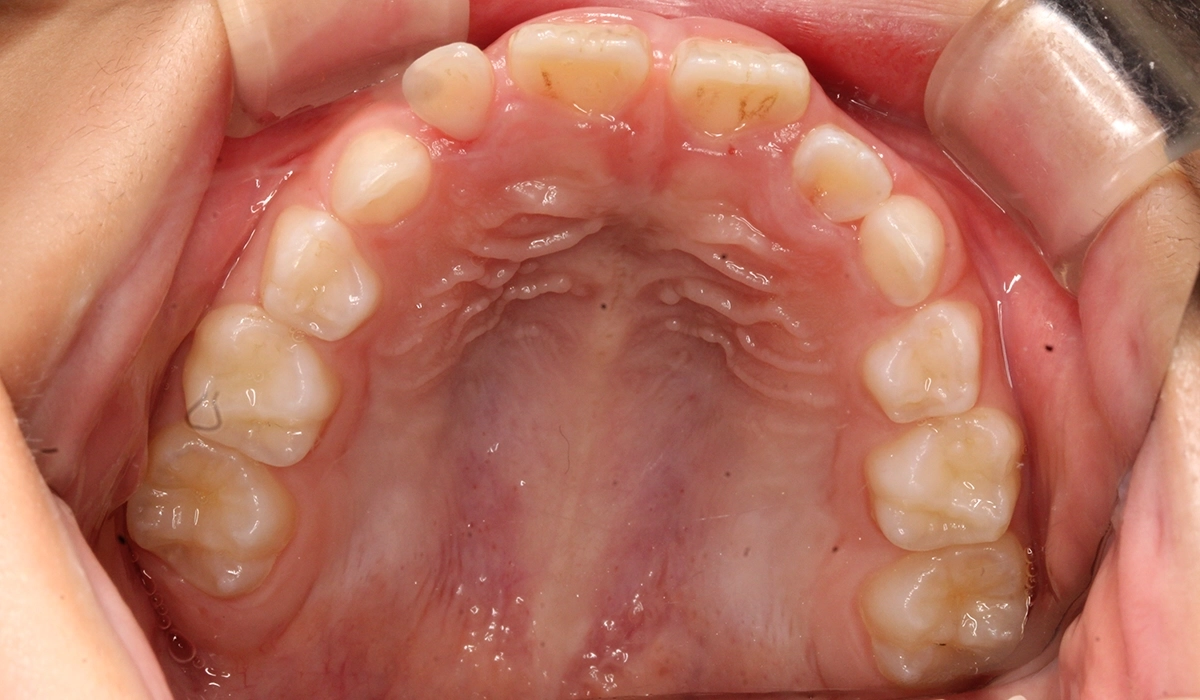

術前:上顎

術後:上顎